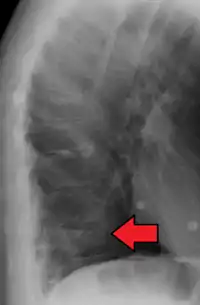

Compression fracture of the fourth lumbar vertebra post falling from a height.

Compression fractures are usually diagnosed on spinal radiographs, where a wedge-shaped vertebra may be visible or there may be loss of height of the vertebra. In addition, bone density measurement may be performed to evaluate for osteoporosis. When a tumor is suspected as the underlying cause, or the fracture was caused by severe trauma, CT or MRI scans may be performed.